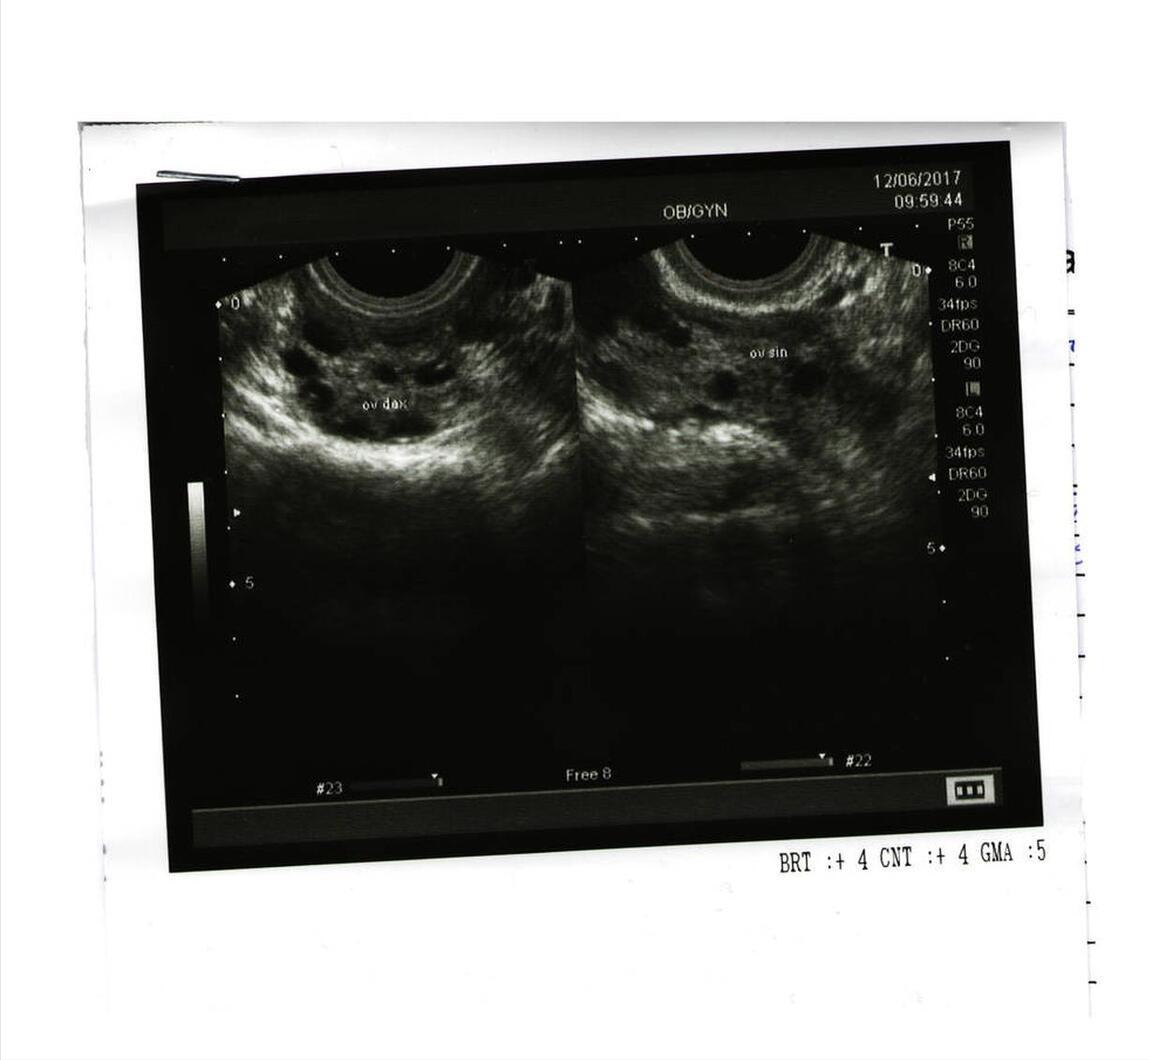

晓茹是一名高一学生,一天上体育课时,她觉得腹部疼痛难忍,老师把她送到医院。查小便、验肝功能都没有问题,通过B超检查,才发现她的肚子居然长了个比棒球还大的卵巢肿瘤!

卵巢囊肿的发病与环境因素、生活习惯、精神状态等有关,但与婚否没有直接关系。未婚女性发现腰围和腹部异常,如有月经失调、经量减少甚至腹痛等症状时,而且持续无好转,应提高警惕。特别是身材偏胖的青少年女性更需注意。主要是因为青春期是卵巢发育成熟、功能旺盛时期,如乱用激素类补品、饮食不当、压力过大,卵巢都极易受到刺激,发生囊肿。对未婚女性来讲,一年一次妇科B超检查十分必要。

孕早期的妇科检查及超声检查对于尽早发现卵巢囊肿非常重要。如果早期诊断,采取适当保健预防和治疗措施,可以顺利妊娠到足月分娩。孕16 ~ 22周是处理卵巢囊肿的最佳时期,此时子宫还不很大、空间有裕,一般可行剔除术。倘若在孕22周以后或妊娠晚期才发现,则尽可能等待胎儿成熟后,进行剖宫产的同时处理卵巢囊肿。

乔安怀孕7个月的时候,B超发现胎儿的腹腔内有囊性包块,直径约6厘米。一个月后,B超复查结果显示,包块比之前增大了2厘米。究竟是什么东西长在还未出生的宝宝肚子里呢?一家人的心里蒙上了厚厚阴影。